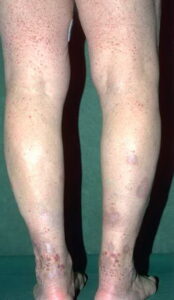

The main symptoms of Allergic vasculitis is nodular erythema occurred in lower limbs, and tenderness can also be associated with purpura, purpuric papules, wind groups, blister dome lesions. Pathological manifestations of the skin vessel walls have inflammatory cell infiltration, mainly polynuclear leukocytes and fibrin deposition, perivascular infiltration of many leukocytes, nuclear dust and red blood cells associated with exudation.

This disease involved only the skin, occur in young adults. General fatigue, joint symptoms such as muscle pain, a small number of cases may have irregular fever. Skin damage can be pleomorphic, with erythema, nodules, purpura, wind groups, blood blisters, papules, necrosis and ulcers. Knees for the most common to the two lower leg and foot up to the back skin lesions. More lesions are characterized by the beginning of purpura-like rash, pressure does not fade is the result of vessel wall inflammation and exudative cell infiltration, and they are high silt from the spot can be touched, is characteristic of allergic Cutaneous vasculitis. Some started to subcutaneous nodules, such as broad beans and soybeans to jujuba size, there is tenderness pink. Purpura may have started to complete the kind of lesions, and some may Erysipelas-like skin lesions began to change, and some may morphea-like changes, and some may like erythema multiforme. The development process in the skin lesions may be accompanied by the wind group, such as papules. As a result of severe inflammatory response in Henoch-Schonlein purpura and rash occurred in blood blisters, necrosis and ulcers, nodules as part of the damage may also occur with painful ulcers. Edema to the ankle and foot for the weight. More pronounced in the afternoon, accompanied by two lower limbs weakness. There are a variety of lesions of this disease, but almost every purpura or nodules. Neutral polynuclear leukocyte extravasation to the surrounding tissue can also occur when the pustules. Lesions can occur at any site, such as the back, upper limbs, buttocks, etc., the distribution was symmetrical. Lesions have a conscious pain, itching or burning sensation, and some without symptoms, and tenderness. After the lesions have more pigmentation and, if after the ulcer can become atrophic scars. Acute episode of disease, the damage to occur in batches, are widely distributed, with lower leg edema, severe illness. After damage from chronic, recurrent sustained a few months or years. Light lesions were 2 to 4 weeks may be more. Some lesions integration to become a large expansion of the damage around the knee, elbow and hands often, it seems erythema lasting performance uplift.